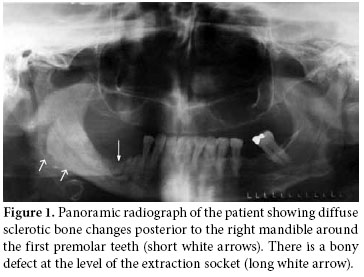

Together with the past history of long-term alendronate treatment and occurrence after tooth extraction, relevant clinical symptoms and conventional radiographic findings led to the suspicion of ONJ in this patient. We immediately ordered dental computed tomography (CT) which revealed sclerosis and osteolytic changes in the right mandible. This confirmed the diagnosis of osteonecrosis (Figures 2, 3). The patient also consulted with dental surgeons, and since there was no pathologic fracture, extra-oral fistulae, or osteolysis extending to the inferior border of the mandible, the disease was accepted to be in the second stage. Surgery was not recommended, and conservative management was started. The patient was advised to discontinue the alendronate treatment, and the etanercept treatment was also stopped. A good oral hygiene regimen using antibacterial tooth rinse was recommended. Her complaints and symptoms alleviated gradually. A control panoramic radiography taken after one year of bisphosphonate withdrawal displayed healing of the exposed bone (Figure 4).